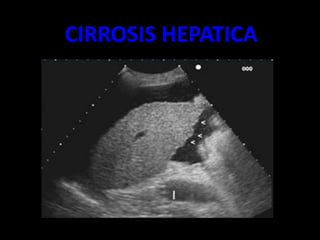

CIRROSIS HEPATICA

• Volumen hepático disminuido, bordes ondulados

• Parénquima con hiperecogenico, formado por ecos gruesos y

con atenuación posterior.

• VP incremento de diámetro, por encima de 14mm.

• VSH disminuidas de diámetro.

• VCI sin latido trasmitido

• Hipertrofia del segmento I, con hipoecogenisidad

• Ascitis

• Esplenomegalia

Ascitis

Bordes ondularos

irregulares

Lobulo hepatico

derecho diminuido

de tamaño